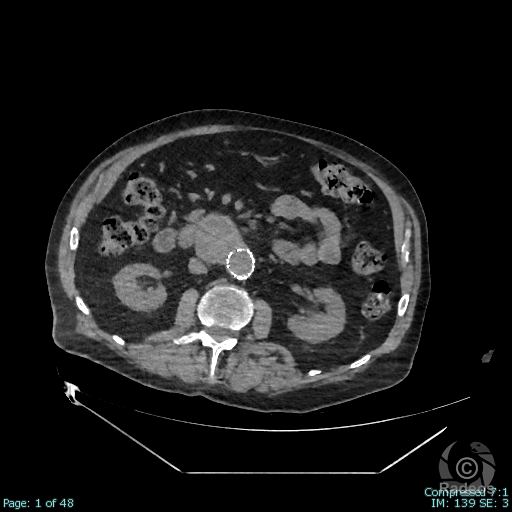

Aspect IRM d'une fibromatose profonde de la paroi abdominale. Découverte fortuite d'un angiome hépatique gauche.

Fibromatose profonde de type desmoïde